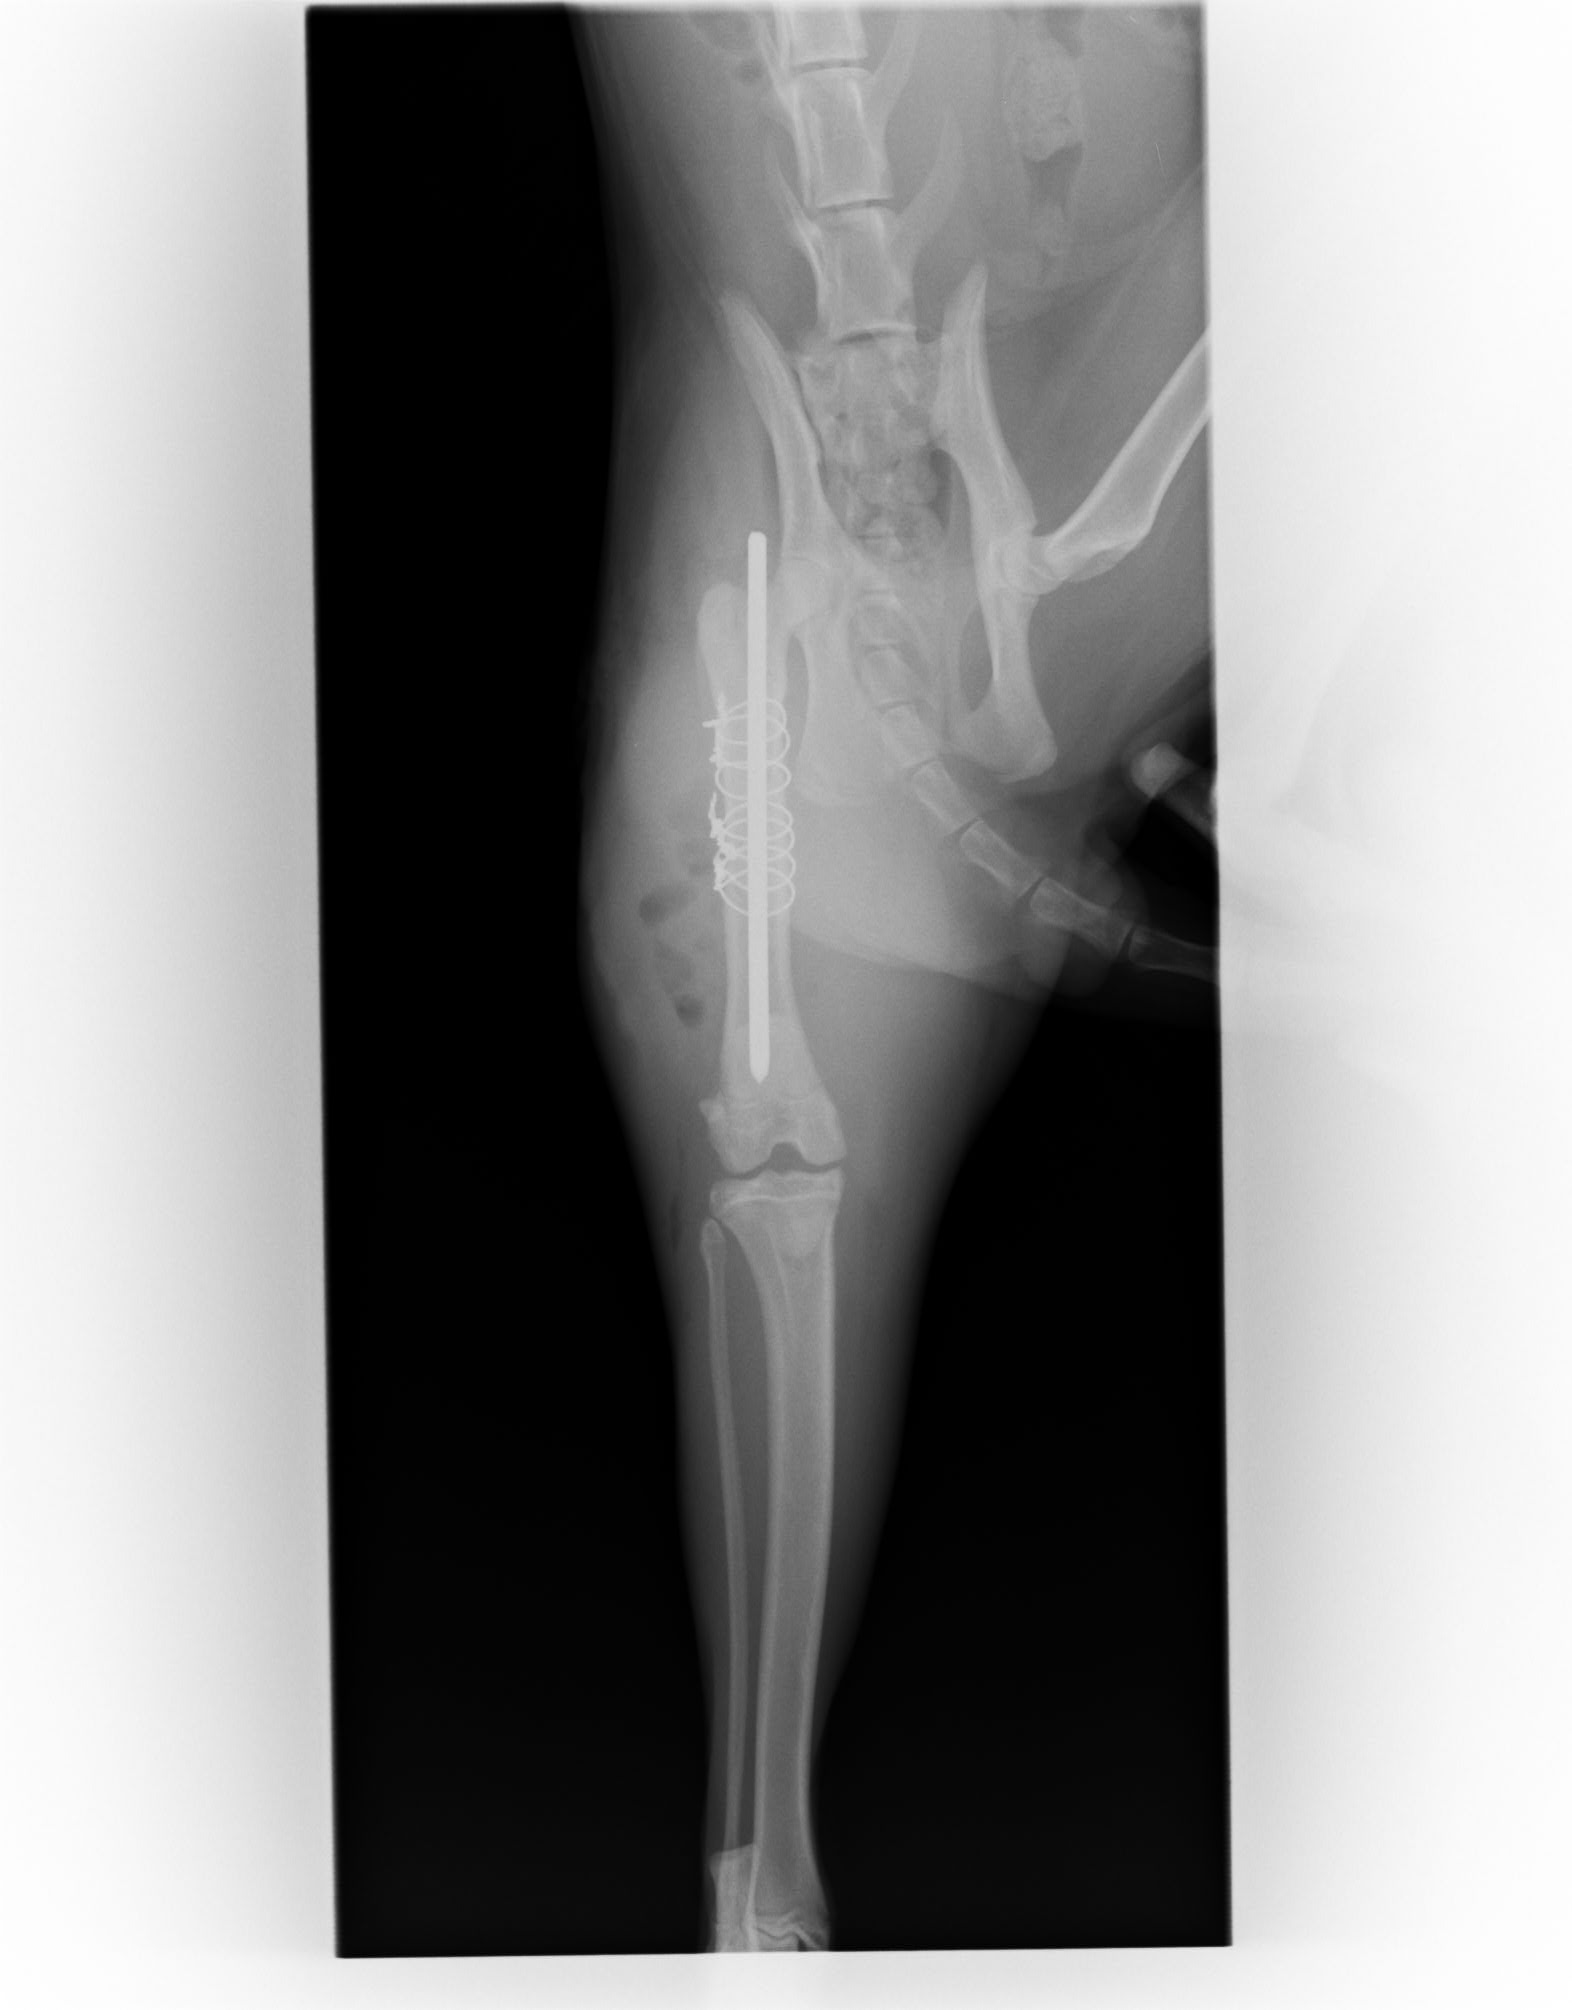

大腿骨の粉砕骨折のため入院し手術を行いました。

手術は無事成功し今では元気にしています。